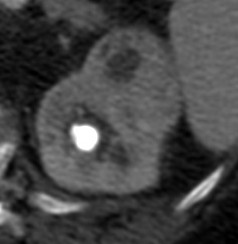

Se procede a realizar TC abdomino-pélvico con contraste en fase nefrográfica y excretora:

- Protocolo: TC abominopélvico sin y con contraste en fase nefrográfica (70 seg) +/- fase tardía ( a los 7 – 10 min) solo si se sospecha obstrucción.

- TC sin contraste permite valorar la presencia de gas, cálculos, hemorragias, aumento del tamaño del riñón, masas inflamatorias y obstrucciones.

- TC con contraste: Las áreas afectadas del parénquima aparecen como zonas con baja atenuación debido al edema. Las áreas hiperdensas son menos frecuentes y corresponden a focos de hemorragia. Estos hallazgos son mejor valorables a través de la aplicación de contraste, ya que un TC en vacío pueden pasar desaprecibidas.